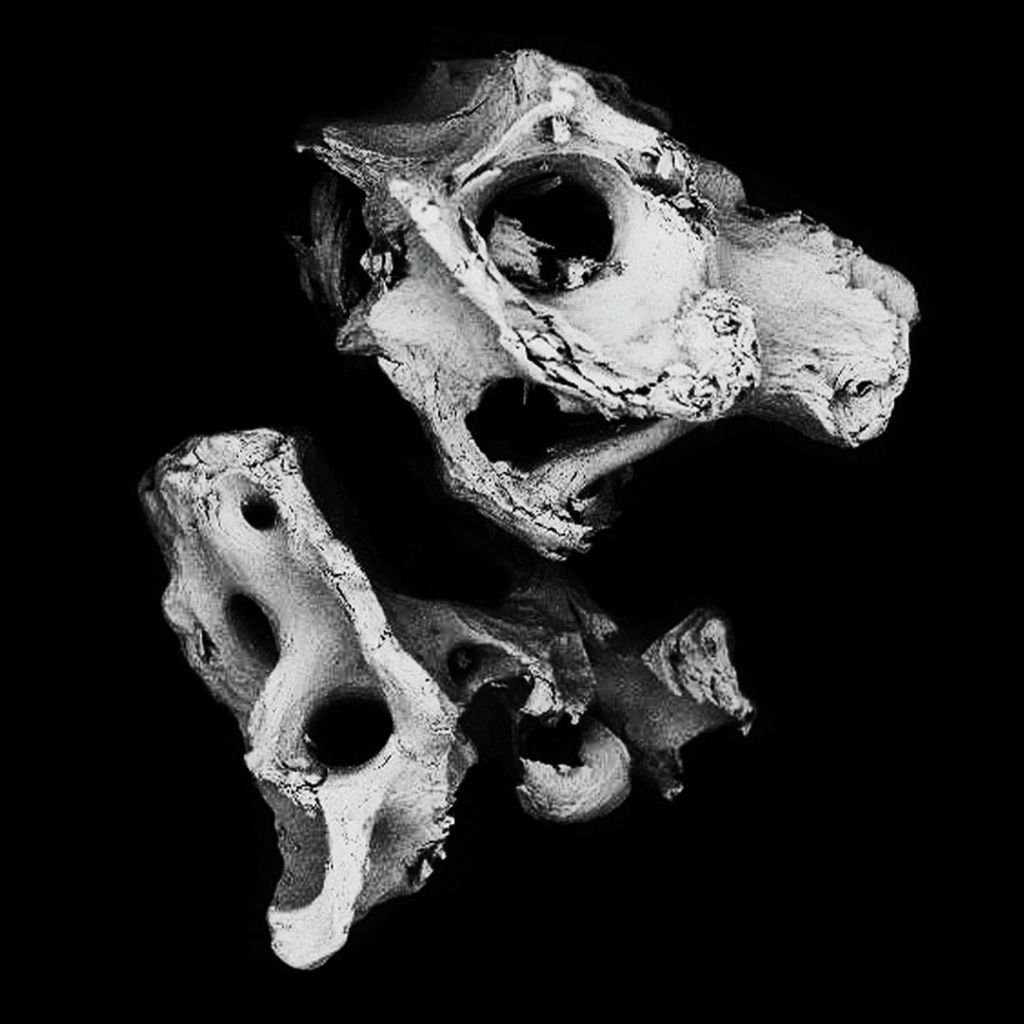

Análisis topográfico.

La microestructura del injerto óseo Bonefill® , analizada mediante SEM/EDS, reveló que el producto presenta una estructura típica del hueso cortical y esponjoso humano, con poros interconectados, y que, tras el proceso fisicoquímico al que se somete la materia prima para su fabricación, conserva la estructura característica de este tipo de tejido. La presencia de poros y el mantenimiento de la estructura cristalina trabecular del hueso son factores fundamentales para el éxito de los fenómenos celulares de deposición de células osteoprogenitoras sobre el injerto, su reabsorción y la formación de nuevo hueso en su lugar.